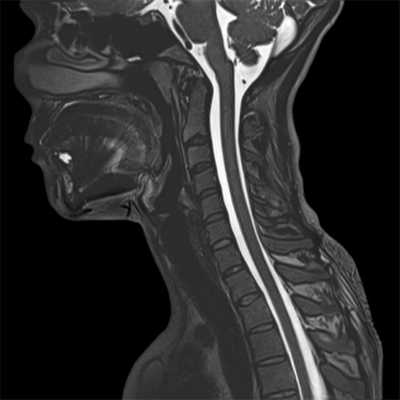

КТ. Перелом тела С2 (красные стрелки).

Особую категорию составляют пациенты, у которых, несмотря на наличие неврологической симптоматики, не выявляется изменений при рентгенографии или КТ. Число таких пациентов составляет около 10%. Среди различных механизмов подобных травм наиболее вероятна кратковременная компрессия спинного мозга задней продольной связкой и дисками, либо, жёлтой связкой и пластиной дуги. Посколько резкие сгибания и разгибания наблюдаются при высокой подвижности в сегментах, такие травмы более вероятны в шейном отделе позвоночника. Спондилолиз усугубляет эту ситуацию, приводя к центральному синдрому спинного мозга. В этих случаях необходимой является МРТ позвоночника. Характерными находками, которые мы часто видим при травмах при МРТ в СПб, являются отёк спинного мозга и гематома, причём последняя при МРТ позвоночника плохим прогностическим фактором в отношении восстановления неврологического дефицита. К наиболее тяжелым осложнениям шейной травмы относится расслоение магистральных артерий, определяемое по МРТ, МРА или КТ и КТА. В высоком поле такой вид травм лучше виден чем в открытом МРТ. МРТ СПб позволяет выбирать место МРТ, однако, острая травма шейного отдела позвоночника требует высокоспециализированного нейрохирургического отделения

МРТ шейного отдела позвоночника. Острая травма. Компрессия спинного мозга, отек и контузия. Сагиттальная Т2-взвешенная МРТ.

МРТ шейного отдела позвоночника. Т2-взвешенная сагитальная МРТ. Острая травма с повреждением задних элементов позвонков и отеком спинного мозга.